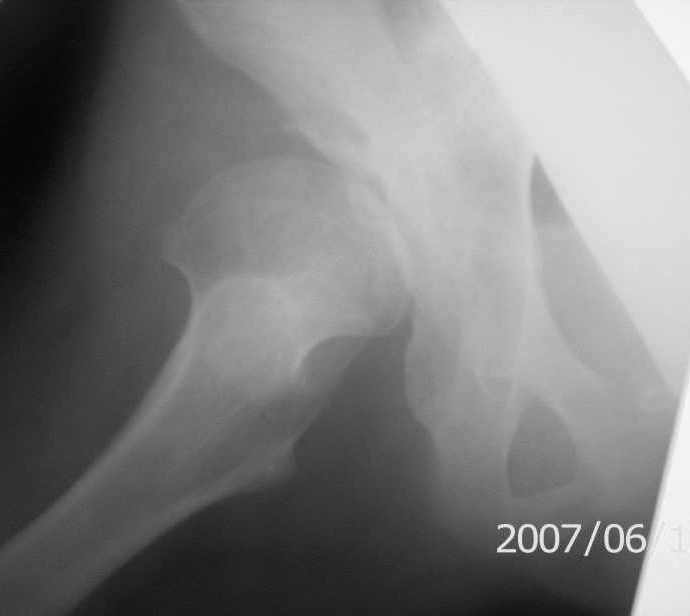

Имя     : п_двивих бокова.jpg